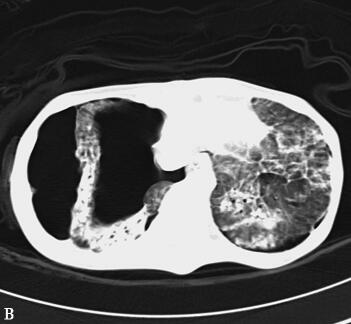

第二阶段(入院后第7~26天):二尖瓣置换术后患者心功能明显改善,多次复查心脏超声均提示心脏舒张及收缩功能未见明显异常,瓣膜功能良好。但患者感染难以控制,考虑感染源:①肺部感染:无法脱离ECMO,胸片提示双肺渗出影(图1),多次痰培养结果均提示鲍曼不动杆菌(MDR);②血源性感染:多次外周血及导管血培养提示洋葱伯克霍尔德菌;③感染性心内膜炎:考虑患者存在急性感染性心内膜炎,瓣膜赘生物形成,多为革兰阳性杆菌感染,但赘生物培养却未见细菌生长。鉴于以上感染相关证据,调整抗感染治疗方案为达托霉素和美罗培南联合左氧氟沙星,并加强气道管理,入院24天后病情明显好转,感染得到控制,逐渐增加呼吸机支持条件,并降低ECMO辅助条件,患者氧合及循环情况均未见恶化,复查胸片渗出较前吸收(图2~图4),故入院后第26天脱离ECMO,在常规机械通气的情况下,患者指脉氧饱和度可维持在95%左右,监测乳酸在1.0mmol/L左右,经皮氧分压88mmHg,经皮二氧化碳分压50mmHg。

第三阶段(入院后第27~46天):患者病情好转,常规机械通气,SIMV和PS模式:Vt 380ml、PEEP 8cmH2O、PS 15cmH2O、FiO2 50%,监测指脉氧饱和度在93%~97%之间,血压在去甲肾上腺素2μg/min持续静脉泵入可维持在110/60mmHg,但出现并发症:①气胸:反复出现气胸(图5A、B),前后共行胸腔闭式引流术8次,随着肺部感染进一步好转,气胸痊愈(图5C、D);②急性肾衰竭:感染性休克导致肾灌注不足,出现急性肾衰竭,持续无尿状态,床边CRRT治疗;③气道出血:患者出现气道出血,予积极止血、气道管理等处理,病情一度好转,但发病后46天患者再次出现气道出血,氧合难以维持,最终死亡。

图5胸部CT(A、B.气胸C、D.气胸痊愈)